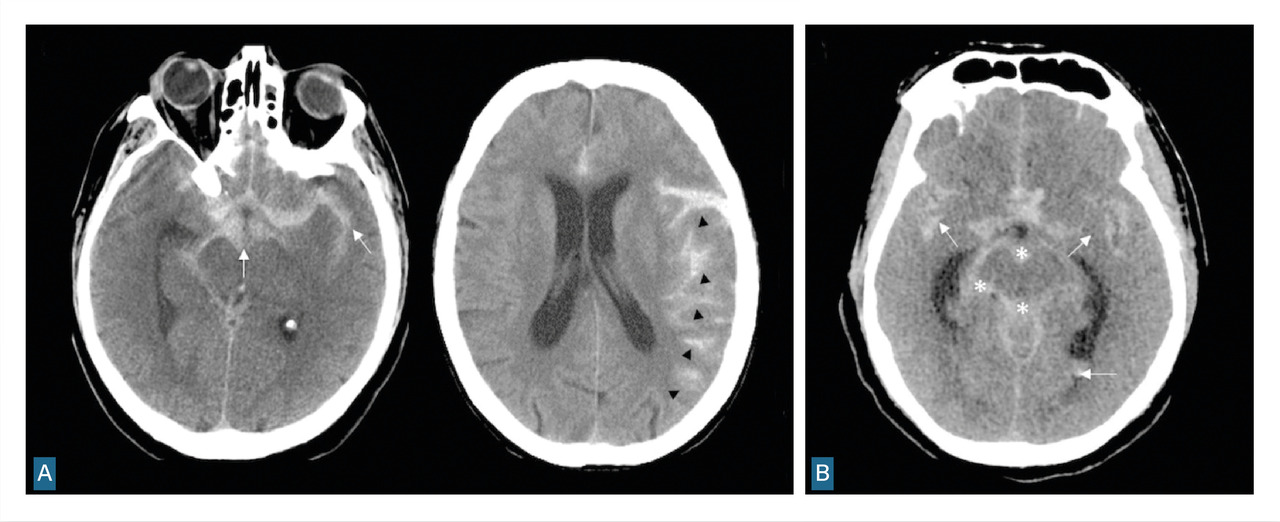

Si l’IRM est accessible et que l’état du patient est compatible, les séquences FLAIR, T2* ou imagerie pondérée en susceptibilité magnétique (SWI) peuvent remplacer le scanner cérébral sans injection (fig. 2), avec une sensibilité plus élevée pour le diagnostic d’hémorragie méningée.